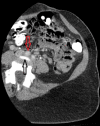

May-Thurner syndrome (MTS) is a rare clinical condition caused by extrinsic compression of the left common iliac vein by the right common iliac artery, leading to venous stasis and predisposing to thrombus formation. Here, we present the case of a 39-year-old female with no obviously known other risk factors predisposing to thrombosis who presented with severe left leg pain and swelling for a week. The international normalized ratio was elevated and the venous Doppler study showed extensive thrombosis extending from the left common iliac vein to the common femoral vein and the popliteal vein. She was diagnosed with MTS and treated with catheter-directed mechanical thrombolysis and thrombectomy, along with angioplasty of the left common iliac vein and external iliac vein, with near-complete resolution post-treatment. MTS should be suspected in patients who present with unilateral limb thrombosis regardless of the presence of predisposing factors. Timely management with endovascular procedures is necessary to help prevent other potential life-threatening complications.